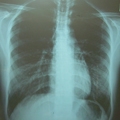

診療案内 HOME 診療案内 肺・呼吸が気になる 肺炎・気管支炎 タバコによる咳・痰(COPD) 長引く咳(咳外来) いびき 胸部異常陰影 生活習慣の改善・指導 動脈硬化の予防 高血圧 コレステロールが高い 糖尿病 痛風(高尿酸血症) 心臓の不調 動悸・ふらつき 胸の痛み 足や顔のむくみ 風邪・胃腸の不調 頭痛・発熱 のどの痛み 胸焼け 嘔吐・下痢 けが・やけど・まき爪 擦り傷・やけど 切り傷 まき爪 打撲・捻挫・突き指 往診・在宅診療 在宅での治療・訪問診療 在宅酸素・人工呼吸器 緩和ケア がん治療についての相談 セカンドオピニン 外来での定期的な検査(手術した病院との連携) 健康診断 特定健診 大阪市 市民がん検診 一般健康診断(自費) 予防接種 予防接種 インフルエンザワクチン 漢方外来・禁煙外来など 漢方外来 禁煙外来